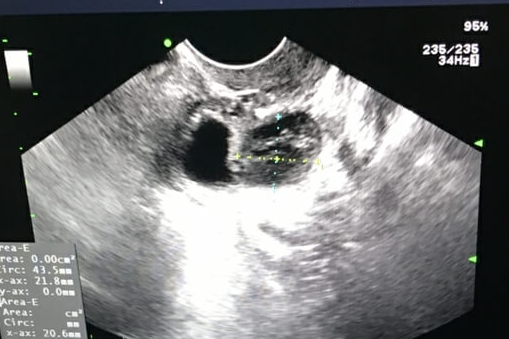

3. 孕早期确认妊娠:阴道B超更安全

移植后14天验血确认怀孕后,需通过B超排除宫外孕并确认胎心。此时建议:

孕5周前:优先阴道B超,可提前1周发现宫内孕囊(腹部B超需孕6周后);